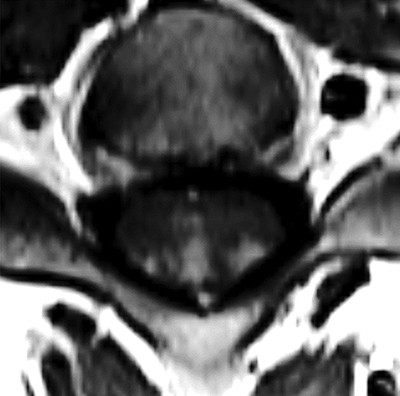

Spinal cord sarcoidosis is a rare condition that can present as a longitudinally extensive transverse myelitis. Current imaging may suggest this pathology, but the final diagnosis relies on the histologic findings. Teaching point: Considering neurosarcoidosis in the differential diagnosis of longitudinally extensive transverse myelitis.

Abstract Image